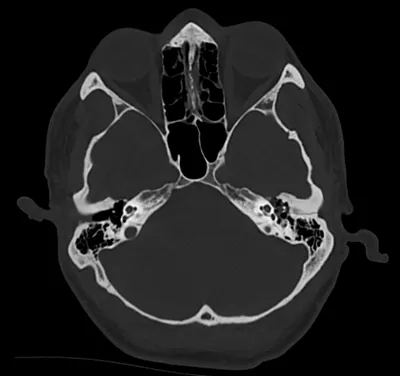

Petrous temporal bone fracture (left)

CTAxialHead+4

2/6/2026